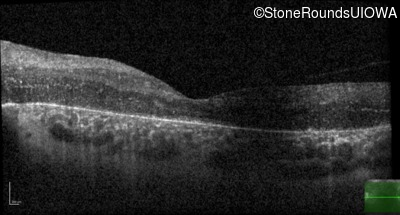

Age at visit: 17 years

This 17 year old female feels that the vision in her right eye has worsened since her cataract surgery 8 weeks ago.